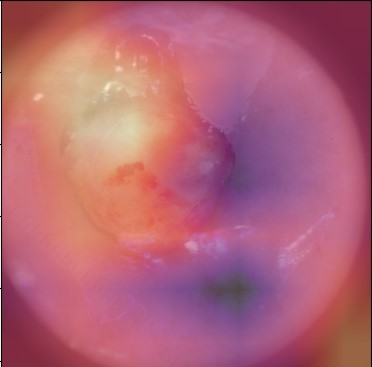

State-of-the-art deep learning approaches for skin lesion recognition often require pretraining on larger and more varied datasets, to overcome the generalization limitations derived from the reduced size of the skin lesion imaging datasets. ImageNet is often used as the pretraining dataset, but its transferring potential is hindered by the domain gap between the source dataset and the target dermatoscopic scenario. In this work, we introduce a novel pretraining approach that sequentially trains a series of Self-Supervised Learning pretext tasks and only requires the unlabeled skin lesion imaging data. We present a simple methodology to establish an ordering that defines a pretext task curriculum. For the multi-class skin lesion classification problem, and ISIC-2019 dataset, we provide experimental evidence showing that: i) a model pretrained by a curriculum of pretext tasks outperforms models pretrained by individual pretext tasks, and ii) a model pretrained by the optimal pretext task curriculum outperforms a model pretrained on ImageNet. We demonstrate that this performance gain is related to the fact that the curriculum of pretext tasks better focuses the attention of the final model on the skin lesion. Beyond performance improvement, this strategy allows for a large reduction in the training time with respect to ImageNet pretraining, which is especially advantageous for network architectures tailored for a specific problem.